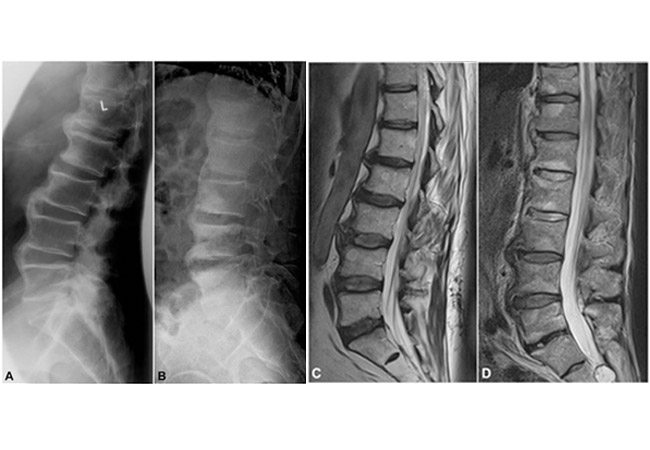

Psoriatic arthritis (PsA) is a chronic autoimmune disease that causes inflammation of the skin and joints. Skin tin go itchy and scaly, and the inflamed joint areas can become stiff, bloated, and painful. It is estimated that as many equally xxx% of people who accept psoriasis volition too develop Psoriatic arthritis. Nevertheless, as it is sometimes activated in the articulation area before symptoms appear on the peel's surface, people can fault it for osteoarthritis (OA) since both forms of arthritis display shared symptoms of articulation hurting, swelling, stiffness, and reduced flexibility. In this commodity, we volition be looking at psoriatic arthritis vs osteoarthritis radiology, causes and symptoms, and other facts yous should know about the two forms of arthritis.

The risk for OA in patients with PsA is significantly higher than for those who exercise not suffer from the condition, with the prevalence of OA being 22.1% in the PsA group. This overlap tin prove difficult when identifying and ten-raying psoriatic arthritis and osteoarthritis. An incorrect diagnosis tin can lead to the wrong treatment of medication and therapy, and as a consequence, the condition worsens. Looking out for symptoms unique to each condition, in addition to radiology procedures, go paw in hand to ensure an accurate diagnosis.